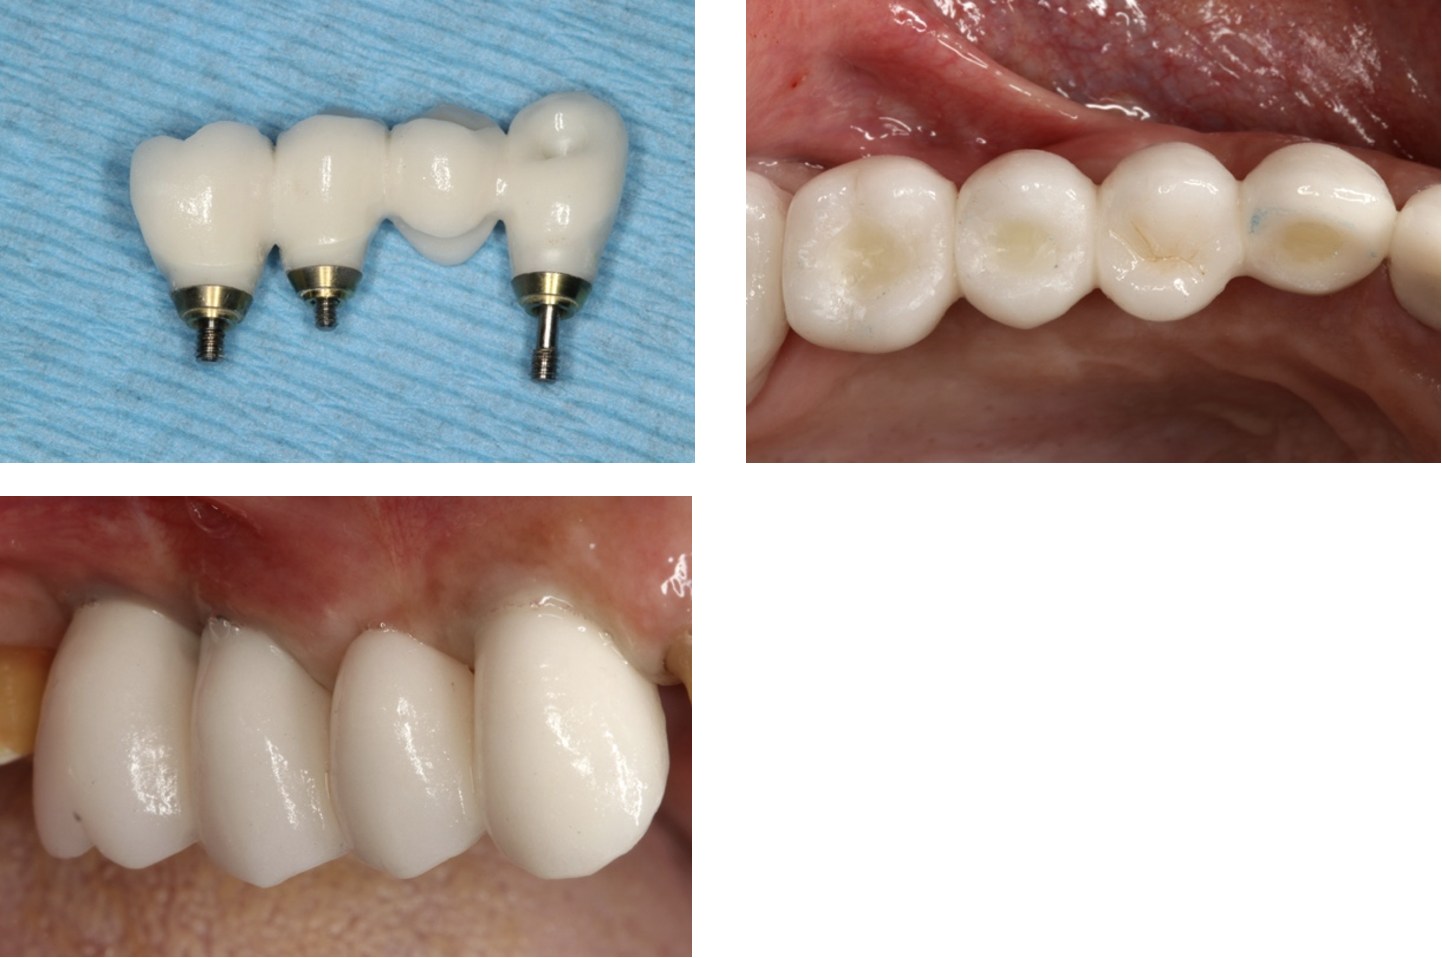

The Result: Optimal Aesthetics and Functionality

The ANGLEBase® solution proved to be a game-changer in this case. It offered a level of flexibility and customisation that greatly enhanced the patient's experience and the overall outcome of the treatment. The aesthetic results were remarkable, and the functionality of the restoration exceeded expectations.

In conclusion, DESS® ANGLEBase® has truly revolutionized our approach to implantology, providing the tools needed to overcome challenges and achieve exceptional results. Its flexibility and precision make it an indispensable part of any dental clinician’s toolkit, ensuring smiles are not only restored but transformed.